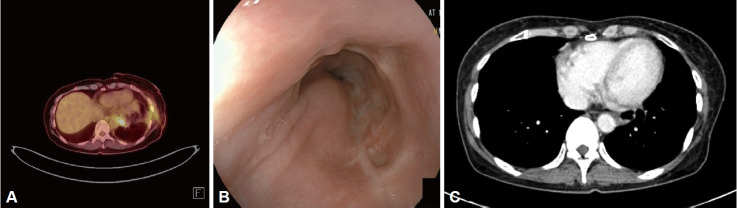

胃肠道间质瘤(gist)是一种罕见的间质肿瘤,主要发生在胃和小肠;而发生在食道的则比较少见。一名54岁妇女因一个月的吞咽困难病史转介至我院。大约5个月前进行的食管胃十二指肠镜检查(EGD)未发现任何特异性发现。然而,在我们医院进行的EGD显示存在一个圆形,突出的病变(大约40×30 mm大小),与正常的粘膜表面覆盖,距离上切牙35-39 cm。胸部电脑断层扫描显示一大块食道肿块。对食管肿块行去核,免疫化学染色诊断为GIST。术后2个月开始给予甲磺酸伊马替尼。术后8个月随访EGD及胸部CT检查,患者病情稳定,未见明显复发。因此,医生应考虑吞咽困难恶化的患者可能有潜在的器质性疾病,如食管间质间质瘤的急性增大,即使近期检查无明显变化。

Gastrointestinal stromal tumors (GISTs) are rare mesenchymal neoplasms that mainly occur in the stomach and small intestine; those arising in the esophagus are rarer. A 54-year-old woman was referred to our hospital with a one-month history of dysphagia. Esophagogastroduodenoscopy (EGD), performed approximately five months earlier, had not revealed any specific findings. However, an EGD performed in our hospital showed the presence of a round, protruding lesion (approximately 40×30 mm in size), with a normal overlying mucosal surface, 35-39 cm from the upper incisor. Chest computed tomography (CT) revealed a large esophageal mass. Enucleation was performed on the esophageal mass, and a GIST was diagnosed using immunochemical staining. Imatinib mesylate administration was initiated two months postoperatively. The patient was stable, without any evident recurrence in the 8-month postoperative follow-up EGD and chest CT examinations. Therefore, physicians should consider that patients with worsening dysphagia may have an underlying organic condition, such as an acute increase in size of an esophageal GIST, even if recent examinations were unremarkable.